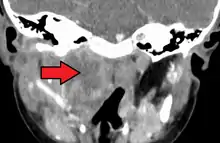

A computed tomography (CT) scan is the definitive diagnostic imaging test.[4]

X-ray of the neck often (80% of the time) shows swelling of the retropharyngeal space in affected individuals. If the retropharyngeal space is more than half of the size of the C2 vertebra, it may indicate retropharyngeal abscess.[5]